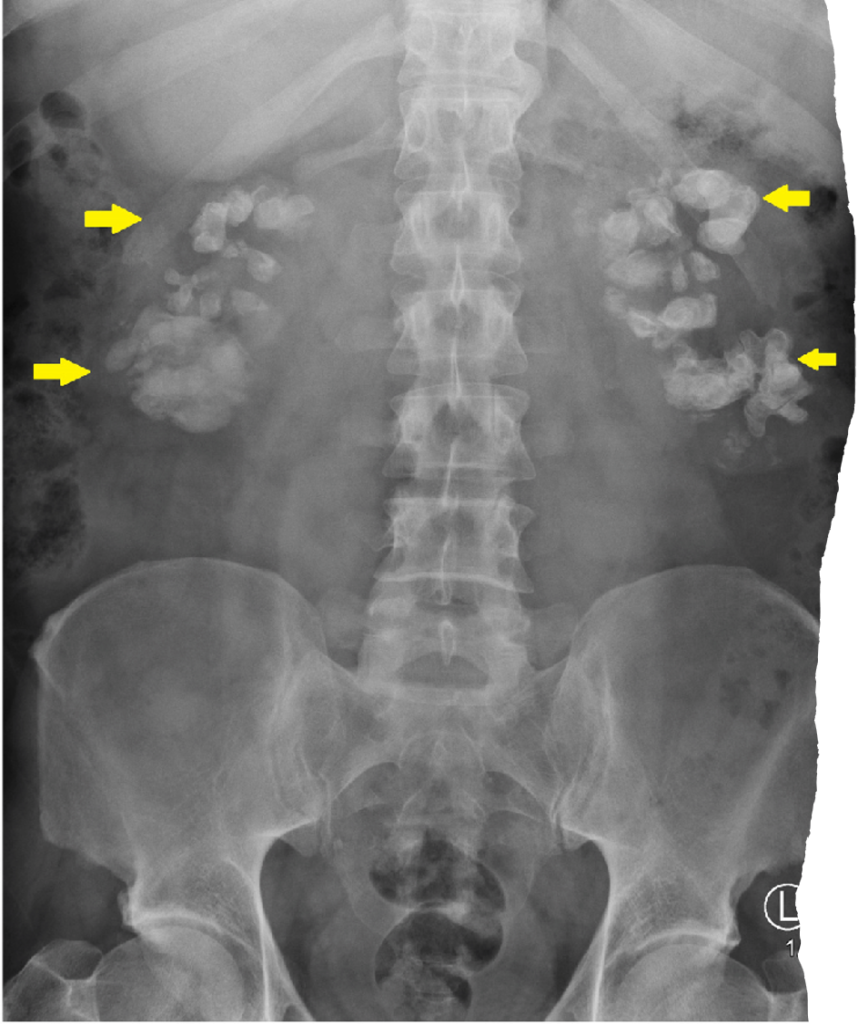

Staghorn Calculus

- Large branching radiopacity occupying renal area.

- Matches collecting system outline.

- Suggests chronic infection and long-standing obstruction.

There is well defined branching radio-opaque calcific density superimposed over the pelvis and calyces of the left kidney.

x-ray KUB of the abdomen. Significant bilateral calcifications are shown to be projected over each kidney.